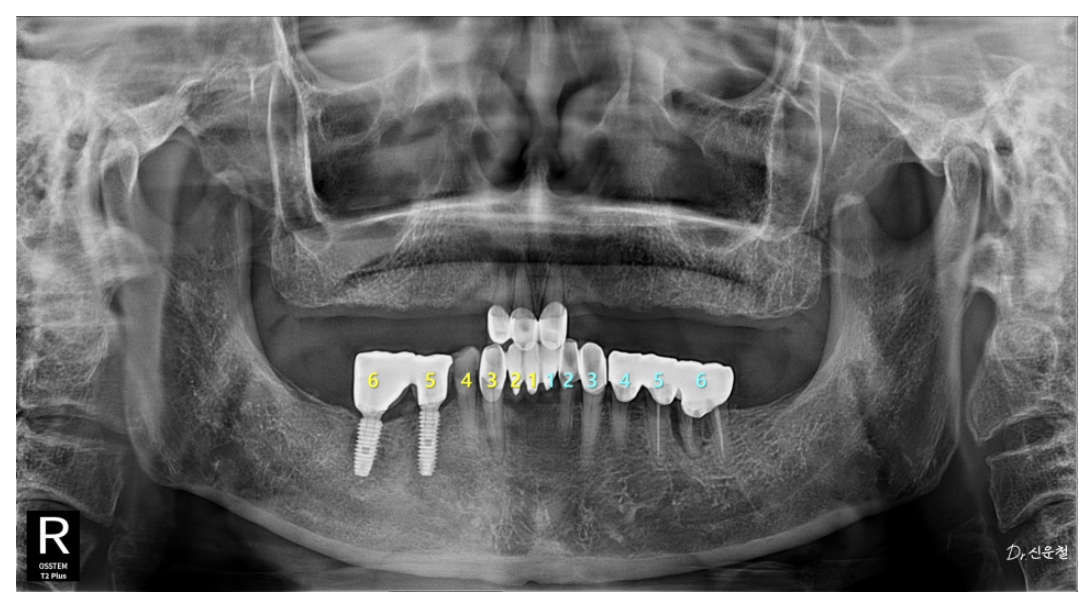

✔ 치료 방향: 총 6개의 임플란트로 기능 회복

치아 기능이 유지되는 아래턱의 범위를 기준으로

위턱 역시 좌우 6개 영역에서 맞춰 균형을 잡았습니다.

즉,

불필요하게 넓히지 않고

힘을 안전하게 지지할 수 있는 최소 범위만 복원했습니다.

[오른쪽 치료 과정]

4개 상실 → 임플란트 3개로 복원

오른쪽은 치아가 4개 연속으로 빠져 있었습니다.

5개 상실 → 안정된 3개로 복원

왼쪽은 앞쪽부터 뒤쪽까지 총 5개가 빠져 있었습니다.

✔ 앞니 2개가 빠져 있어도 ‘캔틸레버’로 한 개만 심었습니다

앞니는 어금니처럼 강한 힘을 받지 않기 때문에

임플란트 1개로도 2개 역할이 충분합니다.

특히 70대 환자분의 경우,

두 자리 중 한 곳은 뼈가 얇아 수술 부담이 컸기 때문에

더 안정적인 위치에만 임플란트를 심고

옆 치아는 자연스럽게 연결했습니다.

캔틸레버(Cantilever):

한쪽만 기둥이 있고 옆 치아는 떠 있는 형태의 연결 방식.